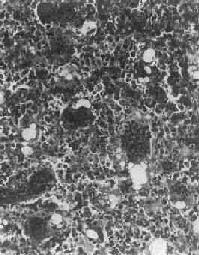

图17-7 硬化性骨肉瘤 股骨干骺端呈梭形肿大,骨干被包埋于中央,周围有清晰的放射状骨梁 骨肉瘤的切面呈多彩状,其外观取决于肿瘤性骨质及软骨的含量以及出血、坏死等继发改变的程度。例如,肿瘤性骨质成分较多时则肉眼观呈黄白色,质地坚硬,有砂粒小点或条纹;如软骨形成明显时则呈半透明状;在肿瘤细胞丰富部位则呈灰红色鱼肉状。 镜下,骨肉瘤由明显间变的梭形或多边形肉瘤细胞组成,细胞大小不等,核形奇异,大而深染,核仁明显,易见病理性核分裂像。肿瘤细胞直接形成肿瘤性类骨组织或骨组织,是诊断骨肉瘤的最重要的组织学依据。所形成的类骨组织或骨组织在不同肿瘤或同一肿瘤的不同部位多少不等。往往可看到肿瘤性骨质发生过程中各阶段的形态,最早期在恶性肿瘤细胞间出现均质红染的胶原样物质,其后红染物质逐渐增多,将肿瘤细胞分隔疏远,构成小梁或片状的肿瘤性类骨组织(图17-8)。类骨组织可伴钙盐沉着,其内的肿瘤细胞固缩变小,形成肿瘤性骨质。骨肉瘤内也可出现肿瘤性软骨(图17-9)。

图17-8 骨肉瘤

图17-9 骨肉瘤 骨肉瘤起源于间叶细胞,形态上表现出多方向分化的潜能,而使骨肉瘤的成分较为复杂。根据其主要的分化成分,组织学上可分成几种类型:最常见者为骨母细胞型,以异型骨母细胞为主要成分,细胞呈多边形,较肥硕,核圆、核仁明显,胞浆丰富,伴较多的肿瘤性类骨和骨组织形成;由软骨肉瘤样组织为主要成分者,属软骨母细胞型;以梭形细胞和胶原纤维为主,似纤维肉瘤者为纤维母细胞型;肿瘤内有许多显著扩张的血管腔隙,伴较多破骨细胞型多核巨细胞,甚似动脉瘤性骨囊肿者为血管扩张型,此型十分少见。在同一肿瘤中上述各种类型的成分常混合存在,但以某一类型为主。不论何种类型,都能见到肿瘤细胞直接形成肿瘤性类骨和骨组织,这是区别于其他骨肿瘤的特征。 【临床病理联系】 骨肉瘤最早的症状是局部疼痛,日渐加剧,持续不断,以夜间为明显。发病2~3月后,局部出现肿胀、质地坚硬。患部皮肤紧张,多呈紫铜色,表面静脉曲张。如骨皮质受侵犯时,轻度外伤即可致病理性骨折。 血清碱性磷酸酶的增高是骨肉瘤的唯一重要化验室检查指征,这和瘤组织内碱性磷酸酶的含量增高相一致,约见于半数病例,对骨肉瘤诊断和推测预后有一定价值。 X线检查对骨肉瘤的诊断有重要价值。常见到肿瘤性骨质形成,表现为云絮状或斑块状密度增高的阴影。这类病例在X线诊断时称为硬化型骨肉瘤。少数病例呈溶骨型,病理上主要为软骨母细胞型和纤维母细胞型以骨质破坏为主,呈虫蚀状或大片状骨质破坏,边界模糊。如前所述,X线检查如发现Codman三角或日光放射状阴影,则对骨肉瘤的诊断很有帮助。 骨肉瘤是高度恶性肿瘤,一般生长迅速,预后较差。局部扩展一方面侵犯骨髓腔及骨皮质,并破坏骨膜及周围软组织;另一方面向骨骺蔓延,甚至扩展到关节软骨。极少数病例可越过关节软骨,侵入关节囊,造成关节活动障碍。近年还发现,骨肉瘤在骨内可呈跳跃性转移(skip metastasis),即在与原发瘤同一骨内的另一处形成孤立性转移结节,甚至还可以转移到相邻的骨内,形成孤立结节,约见于1/4的病例,且不易被X线检查发现,因而预后更差。远处转移多经血道到肺,不少病例在发现原发瘤的同时,即已有肺转移。极少数病例可转移到局部淋巴结。 皮质旁骨肉瘤是骨肉瘤的一种特殊亚型。与一般骨肉瘤不同,本瘤发生于骨膜或骨旁的成骨性纤维组织,瘤体的主要部分位于骨的表面。大多生长缓慢,恶性程度较低,预后远较一般骨肉瘤好,其发病年龄比一般骨肉瘤大5~10岁。本瘤好发于股骨下端的后方,其次为股骨上部。瘤体一般较大,边界较清晰,可呈分叶状。早期对骨质侵犯较少,故易于剥离;晚期可破坏骨皮质而侵犯骨髓腔,但远处转移少见。在切面上,靠近骨皮质或骨膜部分质坚实,而瘤体边缘部分较软,为富于瘤细胞部分。瘤体一般不见出血及坏死。镜下,为分化好的骨肉瘤,成骨现象比较明显。在肿瘤性骨小梁间为增生较活跃的纤维组织,间变不明显,形态上似分化好的纤维肉瘤。少数皮质骨肉瘤分化较差,形成骨质较少,与骨内骨肉瘤相似。